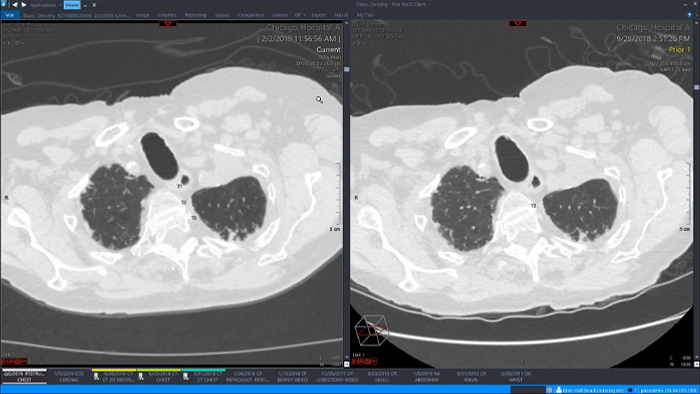

Let’s take a look at some of the immediate benefits of a unified approach. A single, unified workspace for radiology would incorporate advanced 3D post-processing and image distribution capabilities, opened in an additional viewer tab for ease.

A unified workspace would mean that users can easily launch the relevant analysis tools from among the 70+ advanced applications available across multiple clinical domains. Artificial Intelligence can play a role by automating tasks and workflows, predicting usage patterns.

An all-in-one workspace, fully integrated with the enterprise imaging platform and embedded in the diagnostic viewer, offers simple, efficient access to all needed tools across clinical domains. One-click access to advanced visualization tools – such as virtual colonoscopy, 3D processing, and spectral imaging – allows for efficient interpretation and supports diagnostic confidence.

Demonstration of Philips single radiology workspace with advanced visualization